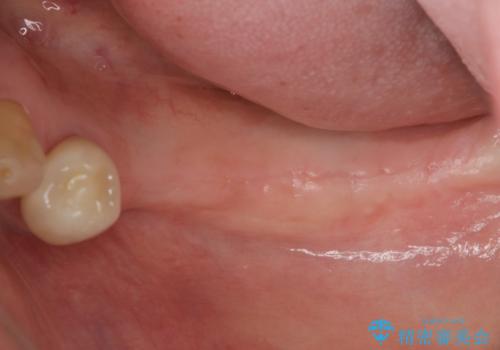

- 長年使っていた入れ歯をなくしてしまい、これを機にインプラントにしようと思い立ち来院されました。

通常長年インプラントを使用すると骨が吸収しインプラント治療が難しくなることもありますが、十分な骨が残っていたためすぐにインプラントの埋入計画を立てることができました。